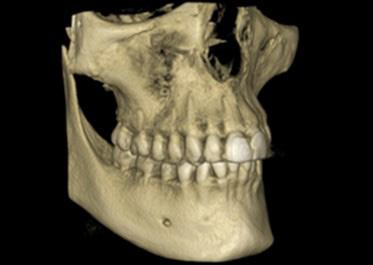

FIG. 4A: Pre-treatment, frontal view

FIG. 4B: Pre-treatment, right lateral view

FIG. 4C: Pre-treatment, left lateral view

FIG. 4D: Pre-treatment, maxilla, occlusal view

FIG. 4E: Mandible occlusal view

FIG. 4F: Pre-treatment, OB and OJ

Clinical dental appraisal revealed full Angle Class II molar and cuspid relationship. The arches were wide and there was a moderate crowding. The patient had 9.0 mm overjet and 6.0 mm overbite. However, the patient reported SDB symptoms, and he also presented with symptoms and signs of TM dysfunction (Figure 4A, B, C, D, E, F))